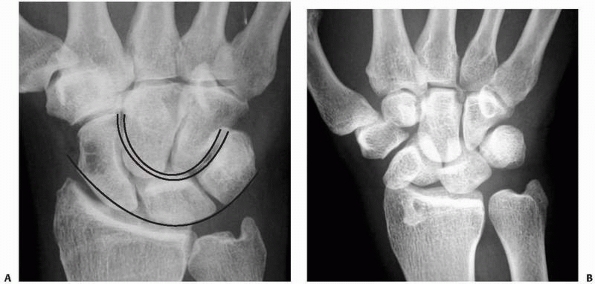

be examined on the AP view. Disruption of these arcs indicates

ligamentous instability.77 The

assessment of Gilula’s line continuity should be a standard in the

evaluation of all AP wrist radiographs to prevent a missed diagnosis of

a perilunate dislocation (Fig. 29-10).

![]() |

|

FIGURE 29-10 Gilula’s lines. A.

AP views show three smooth Gilula arcs in a normal wrist. These arcs outline proximal and distal surfaces of the proximal carpal row and the proximal cortical margins of capitate and hamate. B. Arc I is broken, which indicates an abnormal lunotriquetral joint due to a perilunate dislocation. Additional findings are the cortical ring sign produced by the cortical outline of the distal pole of the scaphoid and a trapezoidal shape of the lunate. |